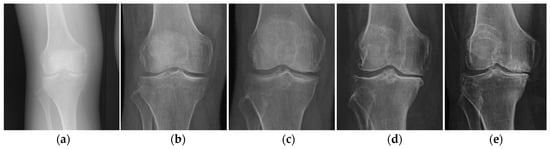

- Kraus, V.B.; Kilfoil, M.; Hash, T.W.; McDaniel, G.; Renner, J.B.; Carrino, J.A.; Adams, S. Atlas of radiographic features of osteoarthritis of the ankle and hindfoot. Osteoarthritis Cartilage 2015, 14, 2059–2085. [Google Scholar] [CrossRef]

- Knee Osteoarthritis: Forms, Diseases, Primary Analyzes, Stages. Available online: https://gp195.ru/bolezni/osteoartrit-lechenie.html (accessed on 15 December 2020).